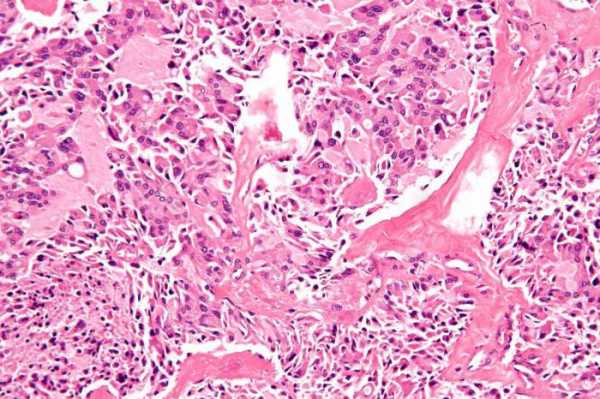

Папиллярная карцинома составляет до 85% от общего количества новообразований злокачественной природы. Опухоль отличается медленным ростом и возникает обычно в одной доле органа. У 15% больных наблюдается двусторонний рак щитовидной железы. Сколько живут пациенты с таким диагнозом, сказать трудно. Новообразование на своей поверхности имеет множество выступов, которые внешне напоминают сосочки. Если исследовать щитовидку у абсолютно здоровых людей, в 10% случаев можно выявить крошечные опухоли. Они никак себя не проявляют, но иногда достигают внушительных размеров, что требует незамедлительного лечения.

Фолликулярная карцинома считается второй по распространенности злокачественной опухолью железы. Заболевание чаще всего выявляют в тех странах, где имеется дефицит йода в пище. Обычно опухоль не выходит за пределы щитовидки, но иногда может метастазировать в другие системы органов. При своевременном лечении больные раком выздоравливают.

Анапластическая карцинома — это весьма редкий вид опухоли, при котором в железе последовательно развиваются нетипичные для нее клетки. Они утрачивают свои первоочередные функции и могут только делиться. Новообразование характеризуется быстрым ростом и распространением по всему организму. Прогноз у больных в большинстве случаев неблагоприятный, рак приводит к летальному исходу.

Медуллярная карцинома составляет 5% от общего числа новообразований железы злокачественной природы. Опухоль может поражать лимфоузлы и легкие. Заболевание сопровождается «приливами», покраснением лица, нарушением стула. Медуллярный рак обычно выявляют у людей после 45 лет. От него в равной степени страдают и женщины, и мужчины. Доказано, что заболевание передается по наследству.

С помощью ультразвукового исследования можно определить размер и точную локализацию опухоли. Так называемый анализ на щитовидную железу необходим для выявления содержания ее гормонов в крови. Цитологическое исследование подразумевает забор ткани опухоли для последующего изучения материала под микроскопом.